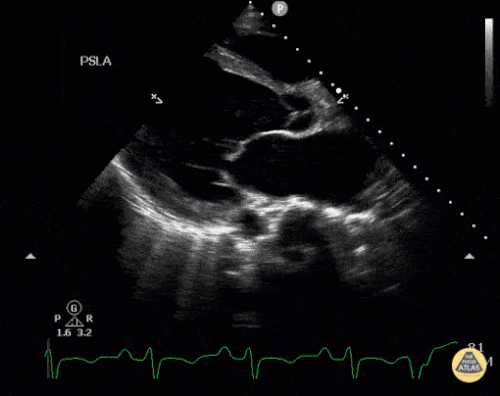

Parasternal uzun aks

Parasternal kısa aks

Sol ventrikül fonksiyonunun değerlendirilmesi

Sol ventrikül (LV) fonksiyonu dört pencerenin tamamında değerlendirilebilir; ancak genellikle parasternal uzun aks görüntüsünde en kolay şekilde incelenir. Değerlendirme iki şekilde yapılabilir:

Görsel (subjektif) tahmin

EPSS (End Point Septal Separation) ölçümü

Azalmış sol ventrikül fonksiyonunu düşündüren hızlı ve pratik bulgular şunlardır:

Sol ventrikül kavite çapının sistolde yaklaşık üçte bir oranında küçülmemesi

Miyokardın sistol sırasında yeterince kalınlaşmaması

Mitral kapağın ön yaprağının diyastolde septuma yaklaşmaması

Buna karşılık hiperdinamik bir kalpte, sistolün zirvesinde ventrikül duvarlarının neredeyse tamamen kollabe olup birbirine temas ettiği izlenir.